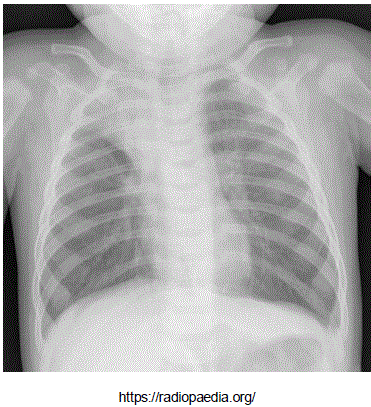

Adolescente masculino, 13 anos de idade, portador de anemia falciforme em seguimento regular com hematologista, apresenta queixa de febre e tosse há dois dias e dor em face anterior do tórax a direta. Ao exame clínico encontra-se em regular estado geral, levemente descorado, FC: 84 bpm, FR: 34 ipm, Saturação de Oxigênio: 95% em ar ambiente, Temp: 38°C, PA: 100/60 mmHg. Realizou radiografia de tórax, que mostrou a imagem abaixo:

Radiografia de tórax realizada há 15 minutos: